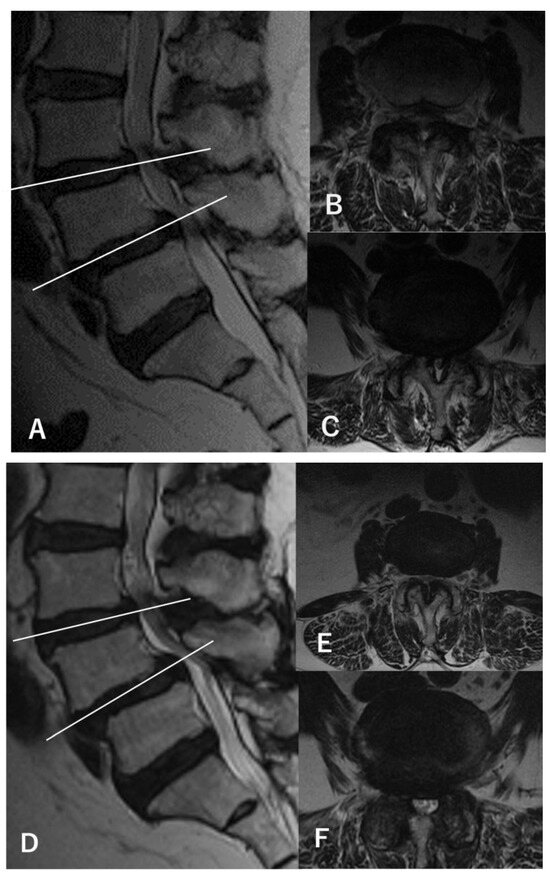

2.1. Definition of L3–4 Stenosis